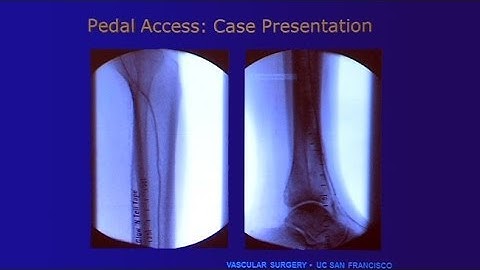

Dr. Fadi Saab, Pedal Artery Access When to Use and How to Avoid Problems